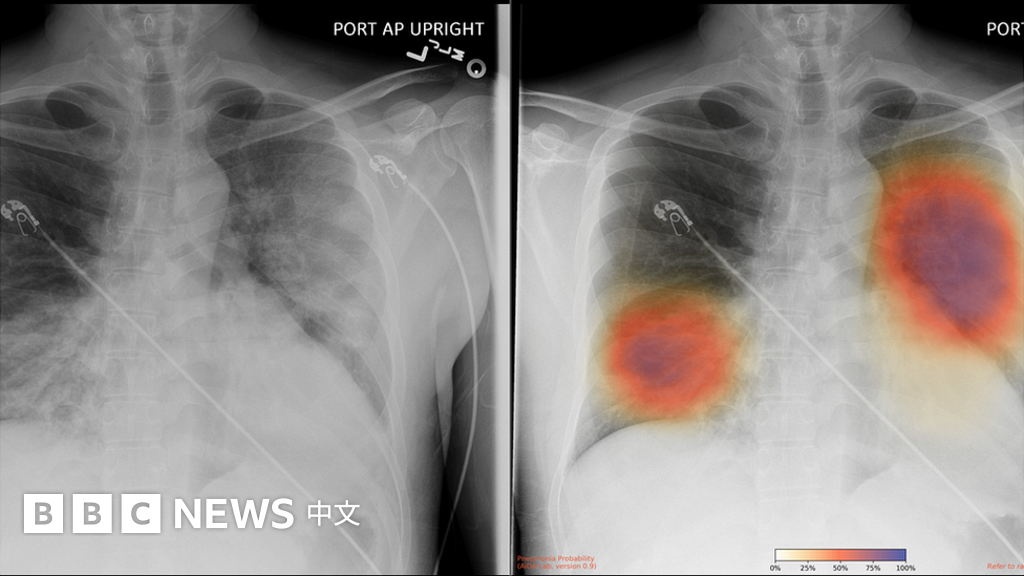

From www.bbc.com

肺炎疫情:人工智能幫助診斷新冠走到哪一步 BBC News 中文 Chest X Ray Detect Coronavirus This rapid advice guide examines the evidence and makes recommendations for the use of chest imaging in acute care of adult patients. the study reveals that infected patients exhibit distinct radiographic visual characteristics along with fever, dry cough, fatigue, dyspnea, etc. Three powerful networks, namely resnet50, inceptionv3, and vgg16, have been fine. Chest X Ray Detect Coronavirus.